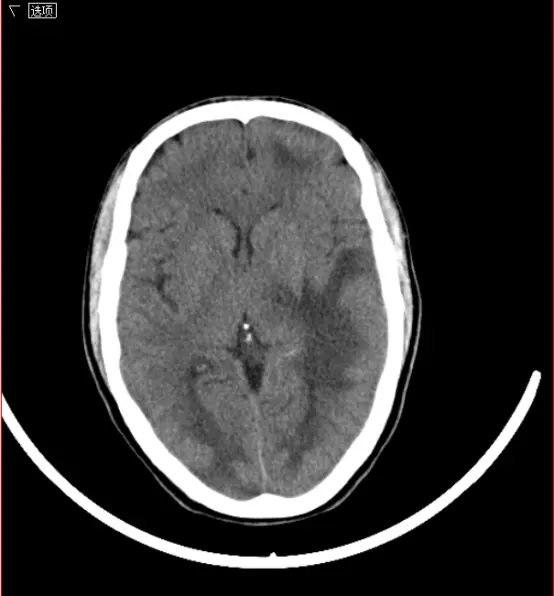

该软件整合了六种分割算法插件,并根据官方文档的说明指出区域生长算法特别适用于分割微小结构如肿瘤及烧结 scar。以下是通过3DMed加载的原始29189000016.dcm图像:

原始图像